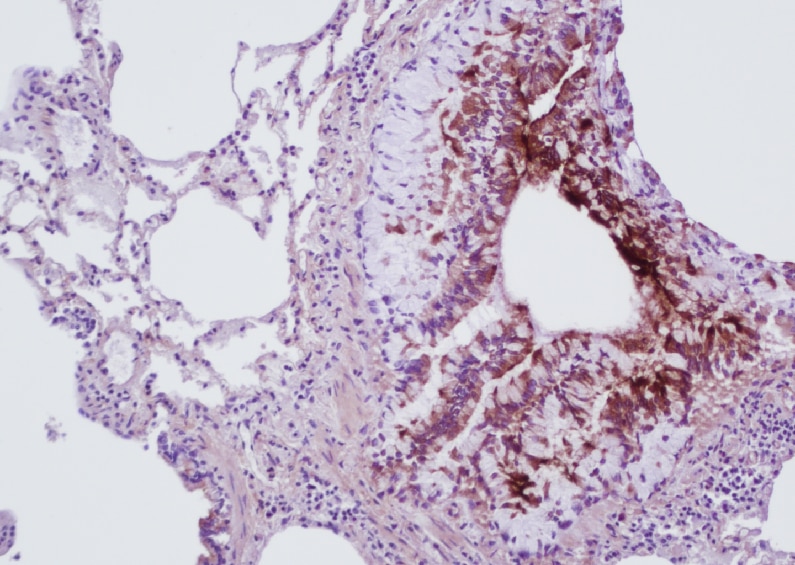

IHC-P | Rat | 05/05/2022 |

IHC-P | Mouse | 10/10/2019 |

IHC-P | Mouse | 10/02/2019 |

IHC-P | Mouse | 10/25/2017 |

IHC-P | Rat | 02/20/2017 |

IHC-P | Rat | 07/20/2016 |

IHC-Fr | Human | 06/18/2013 |

| Federica Gnudi 05/05/2022 |

| Application: | IHC-P | |

| Species: | Rat |

| Verified Customer 10/10/2019 |

| Application: | IHC-P | |

| Species: | Mouse |